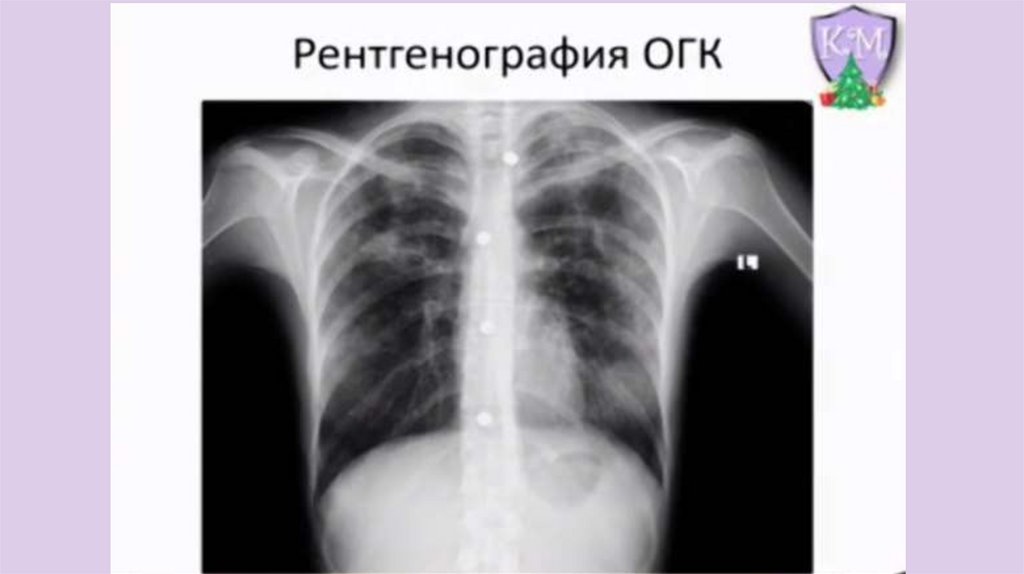

Пациент Н. 50 лет, без сознания.

Предположите причину

17.

18.

Догадавшись, в чем тут проблема, назовите

группу лекарственных препаратов, которые

чаще всего приводят к данной патологии

19.